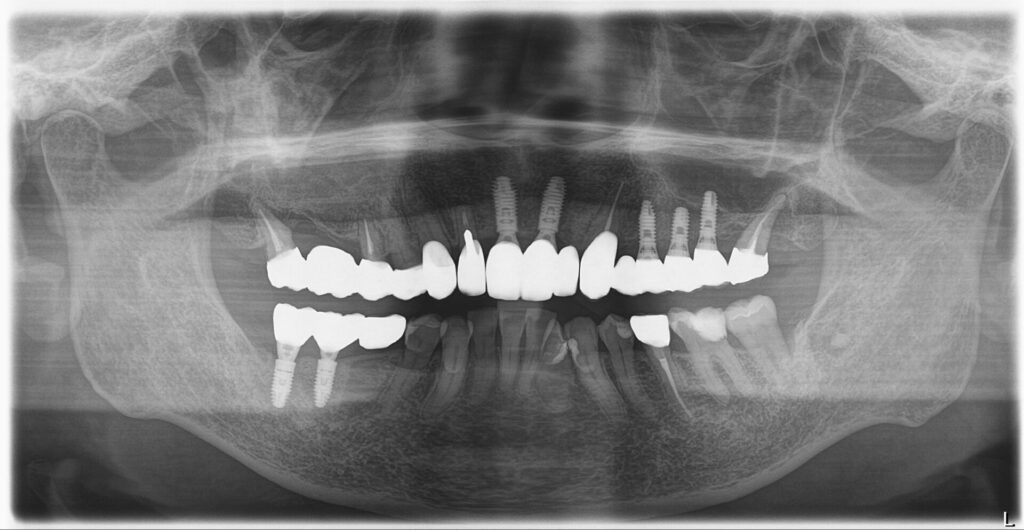

| 治療方法 | ・左上の奥歯と前歯は残せなかったため抜歯をしインプラント手術を行い、治癒を待つ間に仮の歯を入れて噛める状態にしてから右下の奥歯のインプラント手術を行いました。 その後、インプラントと骨がしっかりと結合したことを確認し、ジルコニアボンドを被せる治療を行っています。 ・右上は根がしっかりしていたので、根の治療からやり直し、ジルコニアボンドのブリッジを入れました。 |

| 費用 | ◎インプラント7本埋入 1次オペ代:1,925,000円 2次オペ代:231,000円 ステント(インプラント埋入用ガイド)77,000円 上部構造:1,155,000円 右上ジルコニアボンドブリッジ代693,000円 |